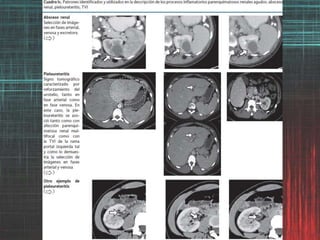

Hallazgos por imagende los procesos inflamatorios del trayecto urinario. La PXG es una variante infrecuente (<1%), atípica y severa de infección parenquimatosa renal. Debido a que sus manifestaciones simulan una neoplasia, el diagnóstico preoperatorio es difícil y si no es considerado por el médico radiólogo como una posibilidad, es referido como un hallazgo incidental por el cirujano o como un reporte de patología.

Hallazgos por imagende los procesos inflamatorios del trayecto urinario. Valor clínico de la graduación de la Pielonefritis aguda (PA) basada en hallazgos de TC -afección parenquimatosa- como factor predictivo de severidad y evolución de la PA. Grado 1 Sin afección demostrable por TC Grado 2 Afección demostrable por TC menor al 25% Grado 3 Afección demostrable por TC mayor del 25% pero menor del 50% Grado 4 Afección demostrable por TC por arriba del 50% Paick SH, Choo GY, Baek M, Bae SR, Kim HG, Lho YS et al. Clinical value of acute pyelonephritis grade based on computed tomography in predicting severity and course of acute pyelonephritis. J Comput Assist Tomogr 2013;37: 440-442